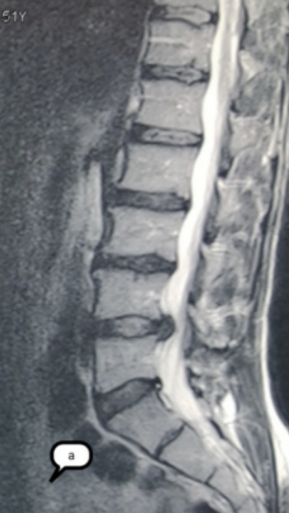

Спондилодисцит L3 – L4

4 процедуры ФДТ, 9 процедур MBST, 20 процедур ИПМТ

Параметры изменяются в зависимости от процедуры